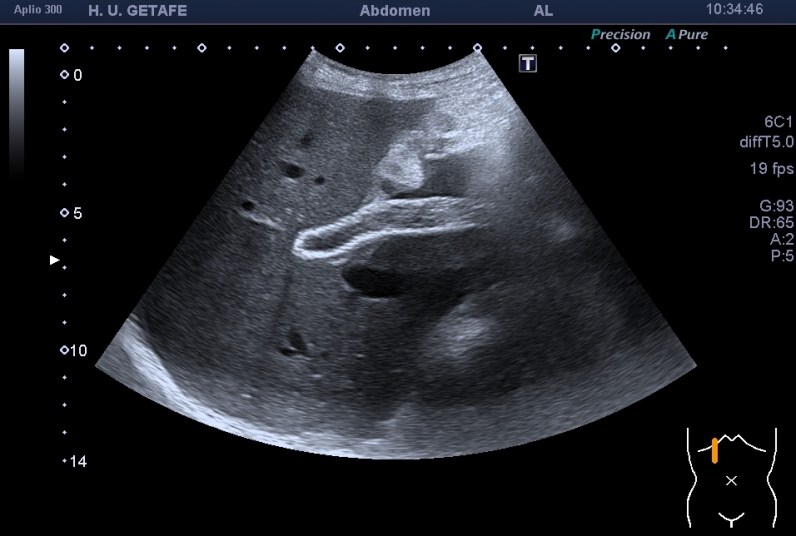

El paciente, diagnosticado de un tumor avanzado en hígado era portador de uno de estos stents que se colocan de forma endoscópica en la sala de vascular de radiología para paliar efectos adversos de aquellos problemas devenidos por el progreso de la enfermedad tumoral que pueda estar ocluyendo el normal paso de la bilis de la vesícula al intestino.

Cuando esto pasa el paciente puede presentar ictericia, pero el caso es que el paciente la presentaba después de haber sido intervenido y posterior a la colocación de dicha prótesis.

La endoprótesis se observa como una ecoarquitectura hiperecogénica con un entramado típico de los stents que se colocan en otras localizaciones cardiacas o aórticas. Se puede observa el aspecto rejilla típico, rodeado de una estructura hiperecogénica que es el cuerpo de la malla y que combate el aumento de la presión producida por el crecimiento de la masa tumoral.